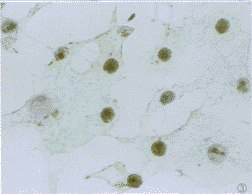

2.1 免疫组化染色结果 正常对照组多数细胞为阴性,仅可见到个别细胞浆内较弱的棕黄色阳性信号(图1)。加热组和病毒感染组于感染后4 h即出现HSP70表达增高,在多数细胞胞浆内可见棕黄色颗粒(图2),尤以细胞核周围更明显,加热后8 h组可见HSP70阳性信号出现在细胞核内,充满整个胞核(图3),胞浆中仅见少许阳性颗粒。而感染组则在核仁区出现阳性信号(图4),加热后24 h组HSP70表达接近正常,而病毒感染组仍可见较多细胞胞浆内阳性颗粒,但信号较前减弱,且核仁内阳性信号消失,感染72 h、5天后部分细胞胞浆内仍有阳性信号,但强度减弱,

图1 正常组Vero E6细胞免疫组化染色,示HSP70阴性.SABC×200